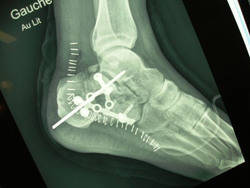

The 37 year old bass player was on holiday in the South of France with his family when he fell from the first floor of their apartment while sleepwalking.He has been recovering in a specialist spinal unit in Toulouse since and underwent surgery to repair two vertebrae and a smashed heel.